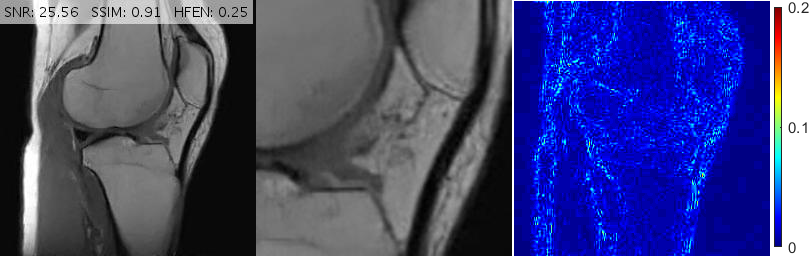

Fig. 6 depicts the reconstruction results for above setups. As attested by the magnified views and error metrics inserted to the top of each reconstruction, TV and TGV significantly degrade the reconstructed image in the rotated setup while RITV gives a remarkably consistent and high-quality result which is hardly distinguishable from the upright solution (note that HFEN and SSIM indices do not change in RITV after rotation). Of course, the upright and rotated directions are only chosen relatively and can always be swapped, nevertheless, the point is TV and TGV fail in at least one of the orientations while RITV succeeds in both. Note that if the selected MR image and Cartesian mask are denoted by and respectively, then a simple machine-aided computation shows that . Therefore, even though the norm-preserving assumption of Theorem 2.1 does not hold true in this experiment (and in fact in many practical situations), the result of RITV is still incredibly isotropic.

Fig. 11 shows reconstructions for an FSE sagittal knee slice under 16% radial sampling. Solutions provided by TGV+Sh, pFISTA, GBRWT, DAMP and BM3D give rise to incoherent, streaking and block artifacts observable in the magnified views. Deep ADMM Net, TL and FDLCP provide more acceptable results, however, the proposed method gives the best and sharpest reconstruction.

For convenience, in Figs. 10, 11 and 13 we have inserted the SNR, SSIM and HFEN values for each method to the top of the corresponding reconstructed image. Moreover, some reconstruction errors in compared methods and their corrections in the proposed method are annotated with arrows.